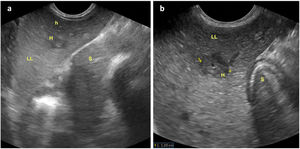

An abdominal ultrasound scan revealed hepatomegaly with periportal hypoechogenicity around the main portal vein and its branches (Figs. 1 and 2), and mild splenomegaly with multiple accessory spleens in the hilum (Fig. 3). The patient was referred to the corresponding referral hospital due to suspicion of myeloproliferative disease, where he received a diagnosis of acute myeloid leukaemia.

Oblique longitudinal plane of the left hypochondrium obtained with a convex probe at the level of the epigastrium, showing: a) Hepatic parenchyma at the level of the left lobe (LHI) with transversal sections of echo-poor periportal haloes of larger (M) and smaller (m) size; b) Enlargement of previous image with measurement of the diameter of one of the periportal haloes. Stomach (E).